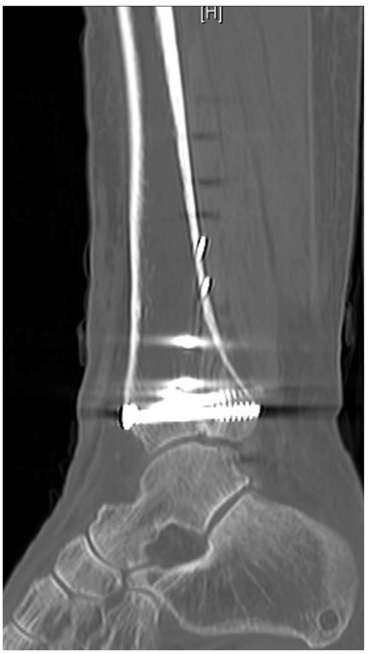

▲后Pilon骨折术后矢状位计算机断层扫描。